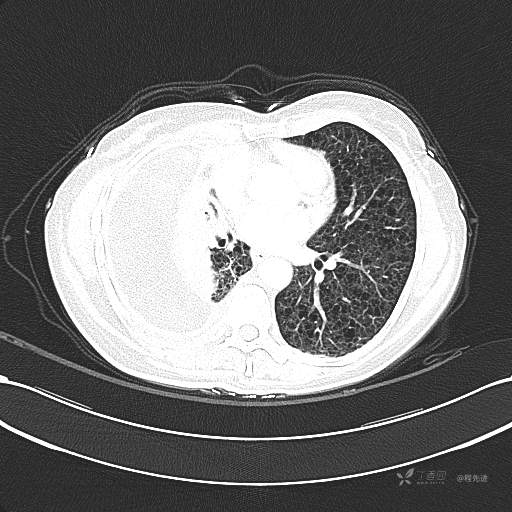

患者性别:女

患者年龄:51岁

简要病史:胸闷半年